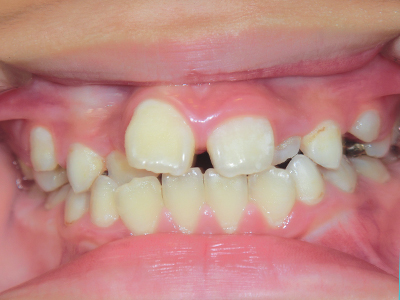

歯並びの相談に来られるお子様は、口呼吸をしているケースが多く、これが歯並びに大きな影響を与えています。

↓ - さまざまな不正咬合が生じる